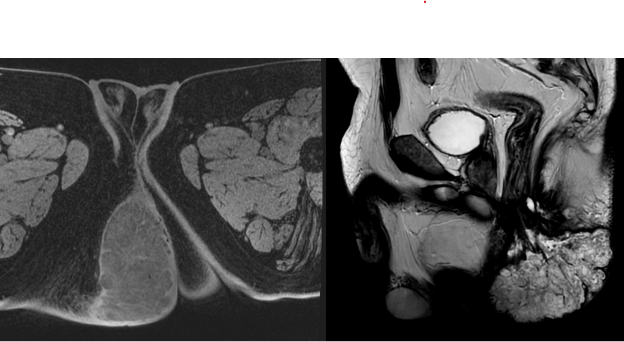

13.6 x 7.5 x 6.2 cm large markedly T2 hyperintense mass extending from the distal anal canal and inferiorly through the anal verge to occupy large portion of the right gluteal cleft.